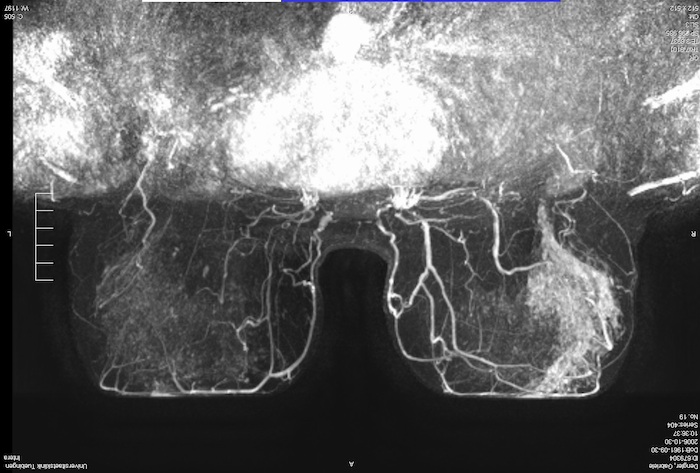

Fibroadenom Sonographisch typisches Fibroadenom mit länglichovaler, gelappter Form bei insgesamt glatter Berandung Das Fibroadenom ist ein gutartiger Tumor der Brust und bedarf in dieser typischen Ausprägung keiner Biopsie, sollte aber über einen kurzen Zeitraum kontrolliert werden. Gutartige Brusttumoren sind Geschwulste der weiblichen Brust, die – je nach Tumorgröße und art – auch verschiedene Symptome hervorrufen können Fibroadenome machen meist keine Beschwerden, da sie in der Regel nicht schmerzhaft sind Die betroffenen Frauen erstasten die harten Knoten meist zufällig oder bei der Selbstuntersuchung der BrustBei sehr schlanken Frauen und wenn der Tumor. Das Fibroadenom meldet sich als „Klassiker“ unter den gutartigen Tumoren der Frau vor der Menopause zumeist sind jüngere Frauen unter 40 Jahren betroffen, mit einem Altersgipfel von ca 25 Jahren Der Tumor ist ein gutartiger Mischtumor, der von der Frau meistens ertastet werden kann.

Ein gutartiger Tumor in der Brust ist eine harmlose Gewebsveränderung und entwickelt sich nur äußerst selten zu einem bösartigen Tumor Nur jedes tausendste Fibroadenom entwickelt sich zu Brustkrebs Trotzdem sollte bei einem gutartigen Tumor die Brust regelmäßig von einem Arzt untersucht werden. Fibroadenom Sonographisch typisches Fibroadenom mit länglichovaler, gelappter Form bei insgesamt glatter Berandung Das Fibroadenom ist ein gutartiger Tumor der Brust und bedarf in dieser typischen Ausprägung keiner Biopsie, sollte aber über einen kurzen Zeitraum kontrolliert werden. Aus diesem Grund wurde angenommen, dass sie das zukünftige Risiko eines bösartigen Tumors nicht erhöhten Die Wissenschafter untersuchten Biopsieproben von 9087 Frauen zwischen 18 und 85 Jahren mit gutartigen Knoten in der Brust, die zwischen 1967 und 1991 in der Klinik behandelt worden waren.